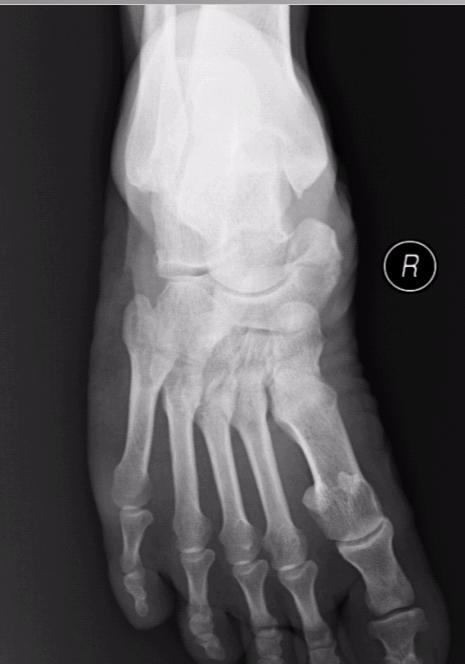

标题: X4772:10年手术 现在复发 足内侧硬肿块,无痛,活动不受 [打印本页]

标题: X4772:10年手术 现在复发 足内侧硬肿块,无痛,活动不受

舟附骨

可不要认为是舟骨骨折呦-----副舟骨---正常表现

副舟骨。

副舟骨,正常改变。如有症状为副舟骨综合症。

副舟骨综合症   是什么啊  老师们告诉我咯

我再次给病人写错了  写的是舟骨术后改变!!!!!!!!!!!!!!!!!!!!!!!!!!!!!还是带教老师让我写的!!!!!!!!!!!!!!!!!